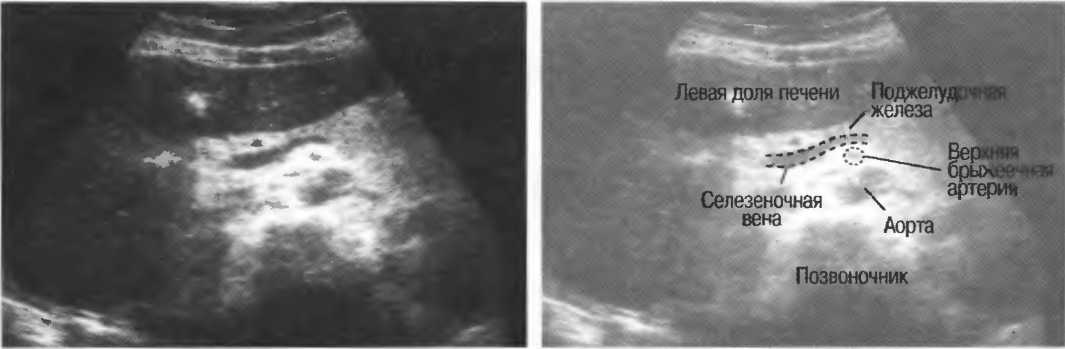

2. Верхняя брыжеечная артерия должна визуализироваться в виде округлого или овального эхонегативного образования, расположенного рядом с поджелудочной железой у здорового взрослого обследуемого (рис. 24). Наиболее простым способом проверки качества изображения является визуализация своей собственной верхней брыжеечной артерии. Сохраняйте эхограммы после каждого исследования для сравнения.

Рис.24. Поперечный срез: верхняя брыжеечная артерия представлена эхонегативным округлым образованием, окруженным эхогенной жировой клетчаткой, расположенным близко к поджелудочной железе.